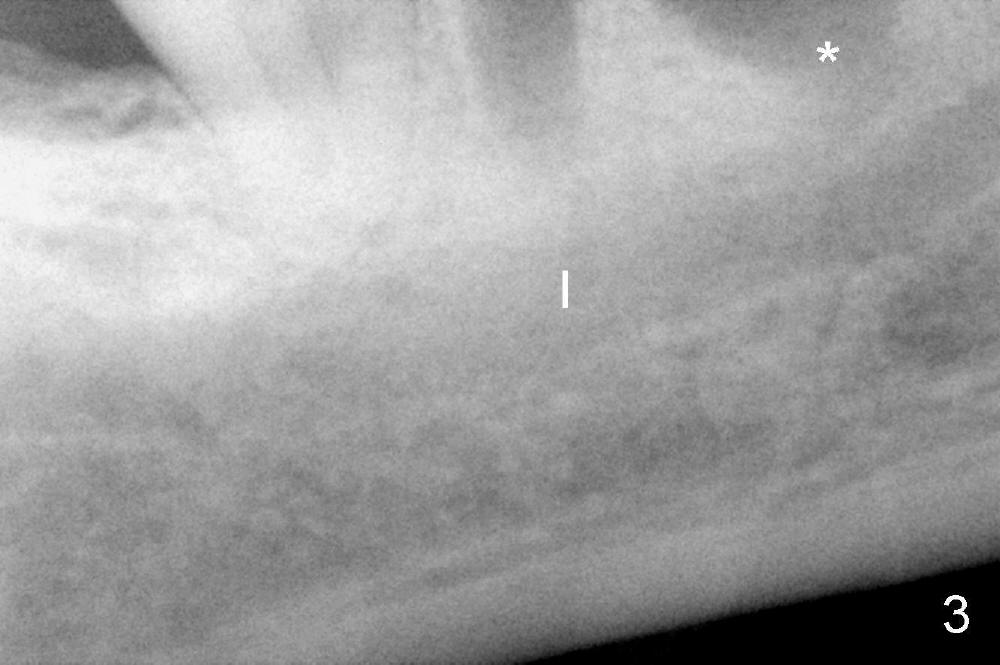

There are three potential spaces for the immediate implant: the mesial and distal sockets and the septum.  First at all, the tooth should be extracted with curettage of granulation tissue from the mesial apical lesion.  The latter turns out to be difficult, since the bottom of the mesial socket has abrupt transition into a narrow neck, which look and feels like the IAN.  To determine the depth of the lesion relative to the IAN, PA is taken (Fig.3) without too much information.  When a radiopaque material in placed in the mesial socket (Fig.4 M), the lesion has apparently not extended to the IAN.  Curettage of the remaining granulation tissue is now an easy task.  Finally bleeding comes from a small hole, as indicated by arrowhead.  Therefore the special structure is a branch of the inferior alveolar vessels.